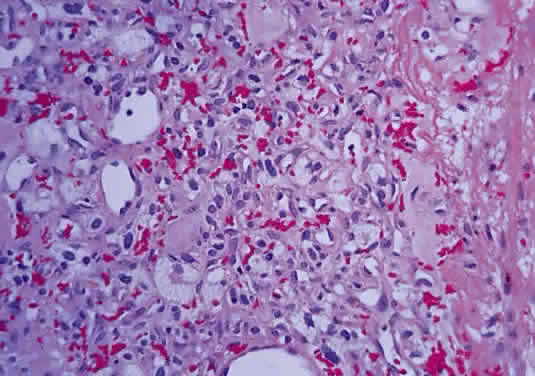

Intraoperatively, hemangioblastoma appears as a reddish, circumscribed tumor that typically is well demarcated from the nerve, although often the central portion is involved. Microscopically, the most striking feature is the abundance of vascular channels, most of which have the appearance of capillaries. Reticulin-staining highlights the vascular network. Between them are stromal cells containing abundant vacuolated cytoplasm, which is due to the presence of lipid. Although bland, the nuclei of the stromal cells are variable in appearance and may exhibit focal marked hyperchromasia (Figs. 46 and 47). Electron microscopy shows that the large stromal cells contain intracytoplasmic particles of lipid and glycogen. Scattered foci of extramedullary hematopoiesis may be present as a consequence of erythropoietin production by the tumor cells. Mast cells also are often readily identifiable. Small cysts are frequent, and the cyst wall consists of gliosis, in which may be found numerous Rosenthal fibers.

Fig. 46. Hemangioblastoma of optic nerve. Multiple capillary vessels are separated by foamy cells (hematoxylin and eosin staining).

Fig. 47. Hemangioblastoma of optic nerve. Foamy cells are a prominent feature between the thin-walled capillary vessels (hematoxylin and eosin staining).